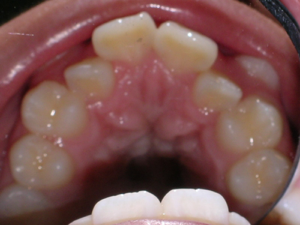

First Premolars were removed. We used an anchor device on the top jaw known as a “Nance” holding arch to help us retract the canines into the first premolar space. The holding device is used to reduce shifting of the top back teeth forward.

Here is what he looked like on the day that the braces were removed.